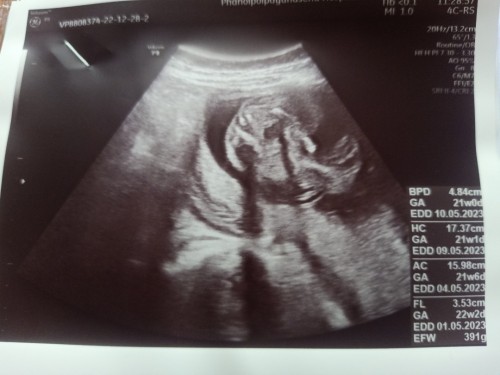

ใครทีมพฤษภาคมบ้างคะ21w ท้อง2 #2-16พ.ค. แม่ๆเดือนไหนกันเอ่ยยยย

22วีคยังไม่รุ้เพศค่ะกำหนด5พฤษภา